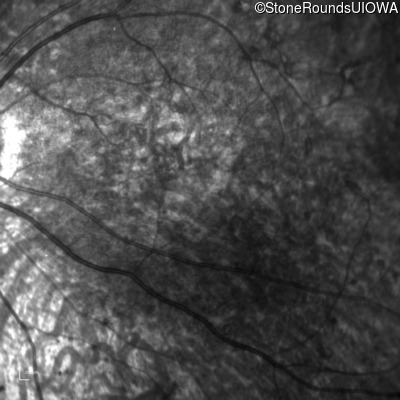

Age at visit: 8 years

This 8 year old girl had normal vision until age 6 when she failed a school vision screening. That year, she was able to play softball well, but this year she often loses sight of the ball and is often hit by it.